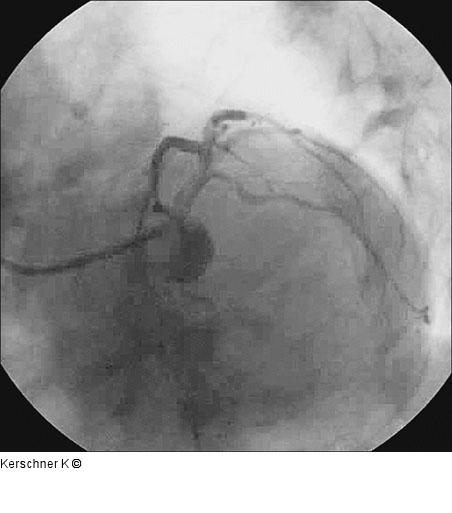

Kerschner K Patient mit Ostiumstenose-Hauptstamm und Bifurkationsstenose - R. interventricularis anterior / R. diagonalis Journal für Kardiologie - Austrian Journal of Cardiology 2005; 12 (9-10): 252 Volltext (PDF) Fallbeschreibung Übersicht

Abbildung 13: Endergebnis LAO/kaudal |